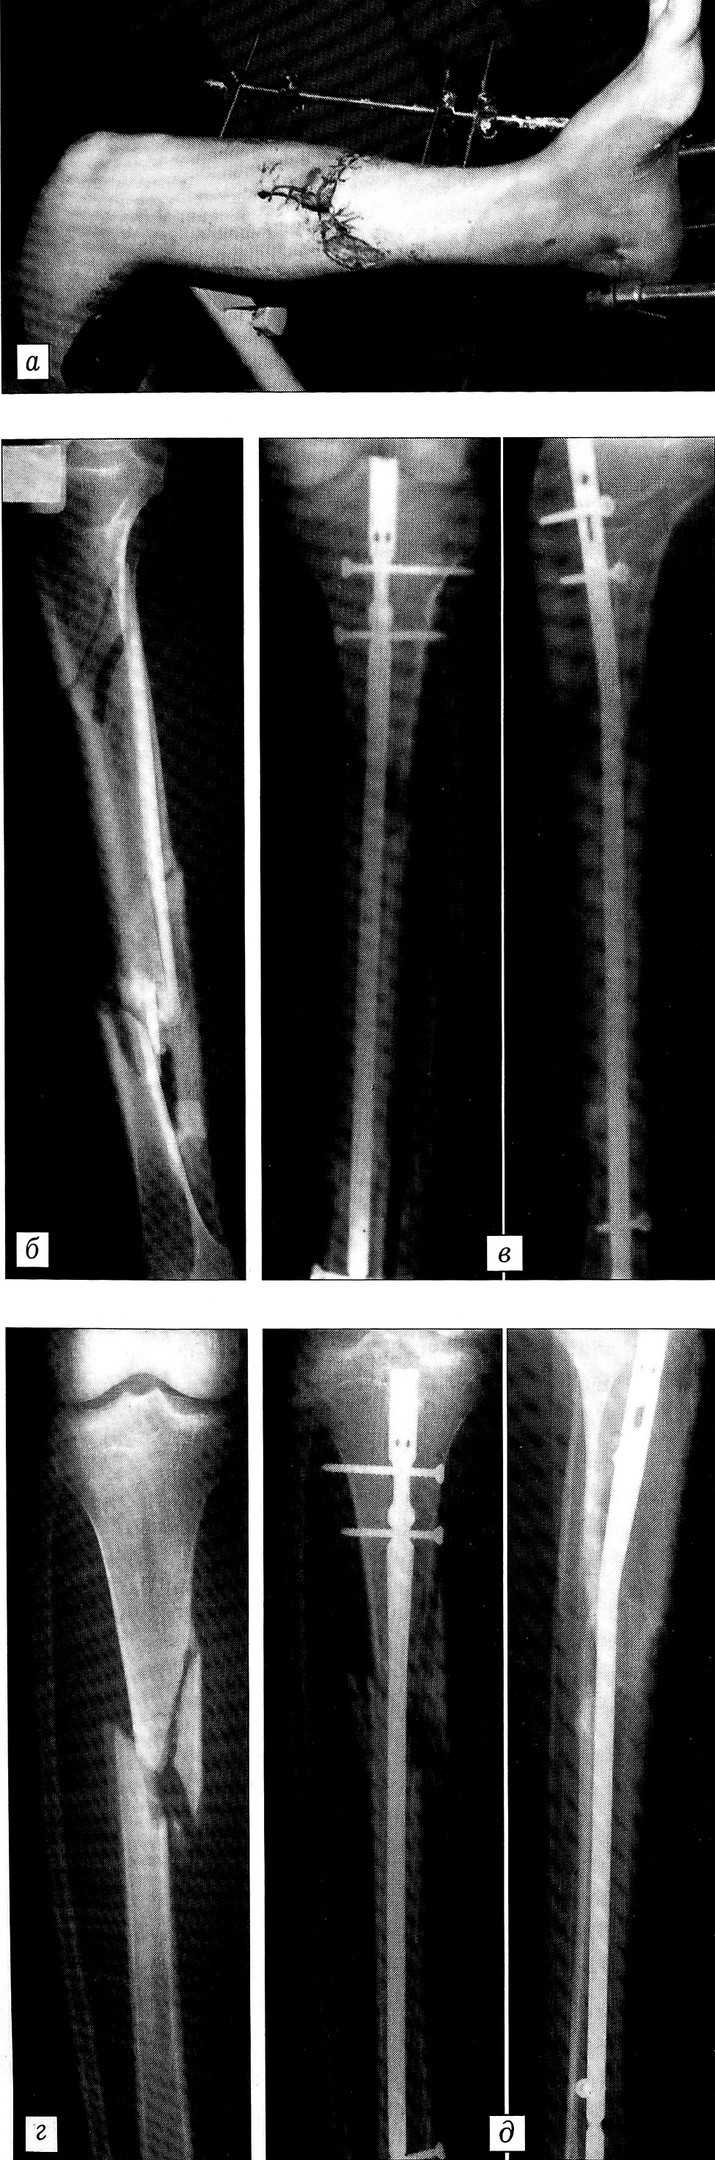

Клинический пример. Больной Г., 38 лет, поступил в реанимационное отделение НИИСП им. Н.В. Склифосовского через 1 ч после получения травмы (сбит автомобилем). При обследовании выявлена тяжелая сочетанная травма: перелом свода и основания черепа, ушиб правой височной доли, субдуральная гематома правой лобно-височной области, эпидуральная гематома заднетеменной области, открытый III степени сложный перелом костей левой голени, закрытый оскольчатый перелом костей правой голени. После стабилизации гемодинамических показателей — через 6 ч с момента поступления больной взят в операционную. Произведена первичная хирургическая обработка раны левой голени, наложен стержневой аппарат наружной фиксации. Перелом костей правой голени фиксирован гипсовой лонгетной повязкой. После первичной хирургической обработки раны левой голени остался дефект кожи 0,5% поверхности тела. Больному проводилась инфузионно-трансфузионная, антибактериальная, иммунокорригирующая терапия, антитромботическая профилактика. Через 9 дней под спинномозговой анестезией при наличии гранулирующей раны на левой голени произведен демонтаж аппарата наружной фиксации и выполнен закрытый блокирующий остеосинтез обеих большеберцовых костей гвоздями без рассверливания костномозгового канала (рис. 2). Ранний послеоперационный период протекал без осложнений. На 19-е сутки с момента поступления произведена аутодермопластика гранулирующей раны левой голени расщепленным кожным лоскутом. Приживление кожного лоскута 100%. На 27-е сутки после травмы больной в удовлетворительном состоянии выписан на амбулаторное лечение. Через 1,5 мес после травмы начал ходить при помощи костылей, через 3 мес — с полной опорой на ноги. Рентгенологически переломы срослись через 6 мес. Больной ходит, не хромая. Движения в суставах конечностей в полном объеме.

Рис. 2. Больной Г. Сочетанная черепно-мозговая травма. Открытый сложный (тип С) перелом левой голени III степени, закрытый оскольчатый (тип В) перелом правой голени.a-e — левая голень: а — перелом стабилизирован аппаратом наружной фиксации. Гранулирующая рана. Голень фиксирована на ортопедическом столе (подготовка к снятию аппарата и закрытому остеосинтезу блокирующим гвоздем); б — рентгенограмма до, в — после закрытого остеосинтеза UTN;г, д — правая голень: рентгенограммы до (г) и после (б) закрытого остеосинтеза UTN.